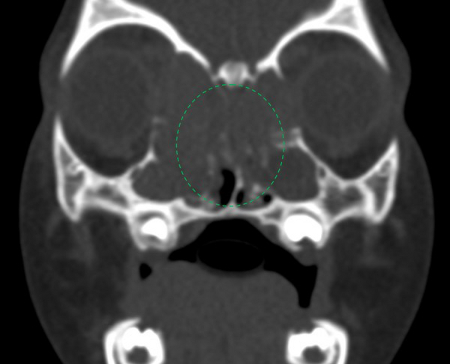

[Figure caption and citation for the preceding image starts]: CT—Coronal view of the paranasal sinuses showing the blockage of the osteomeatal complexes (Green Circle)Mohd Slim MA et al. Paediatric nasal polyps in cystic fibrosis. BMJ Case Rep 2016 Jun 21;2016; used with permission [Citation ends].